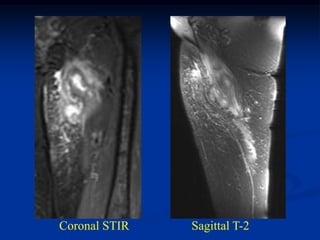

Case #253

29 year male

recent fracture ulna

18 months later

with desmoid tumor

at fracture site

Sagittal T-2 MRI 18 months later with desmoid tumor

Axial T-2 MRI at 18 months